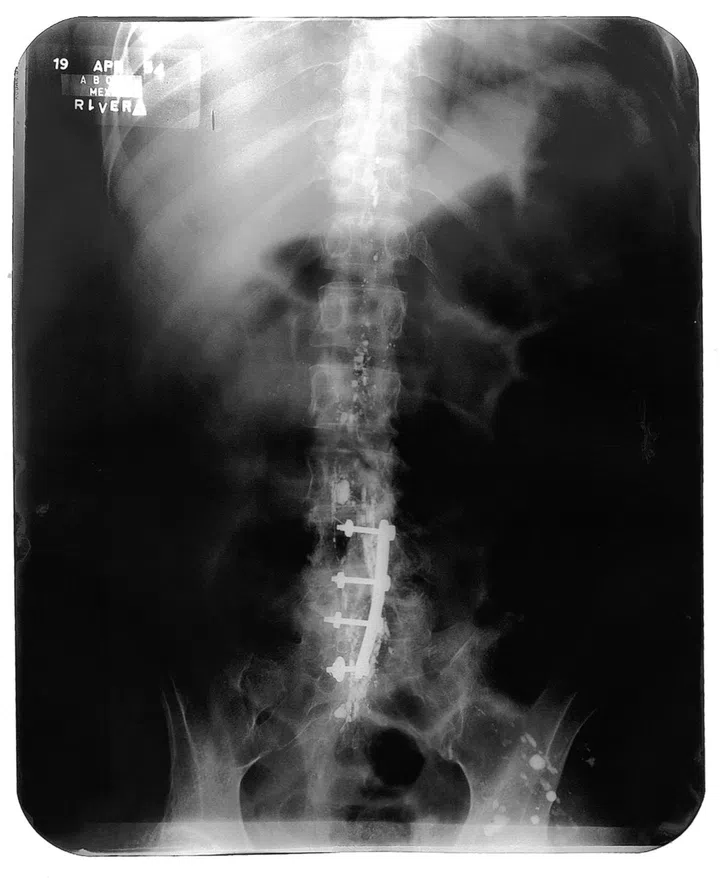

Frida Kahlo一生命运多舛,六岁就诊断出患有小儿麻痹症,18岁因一场意外差点丧命,导致脊椎、锁骨和肋骨骨折,骨盆粉碎性骨折,一只脚也被压碎。大部分时候,她必需忍受着肉体极大的痛苦一边创作。

X-Ray of Frida Kahlo's spine © Banco de México. Fiduciario en el Fideicomiso relative a los museos Diego Rivera y Frida Kahlo

首次展出的Frida Kahlo 脊椎X光片,展方也与本地专科医生合作,附上讲解,让观众能够深入了解Frida Kahlo当时的身体状态。